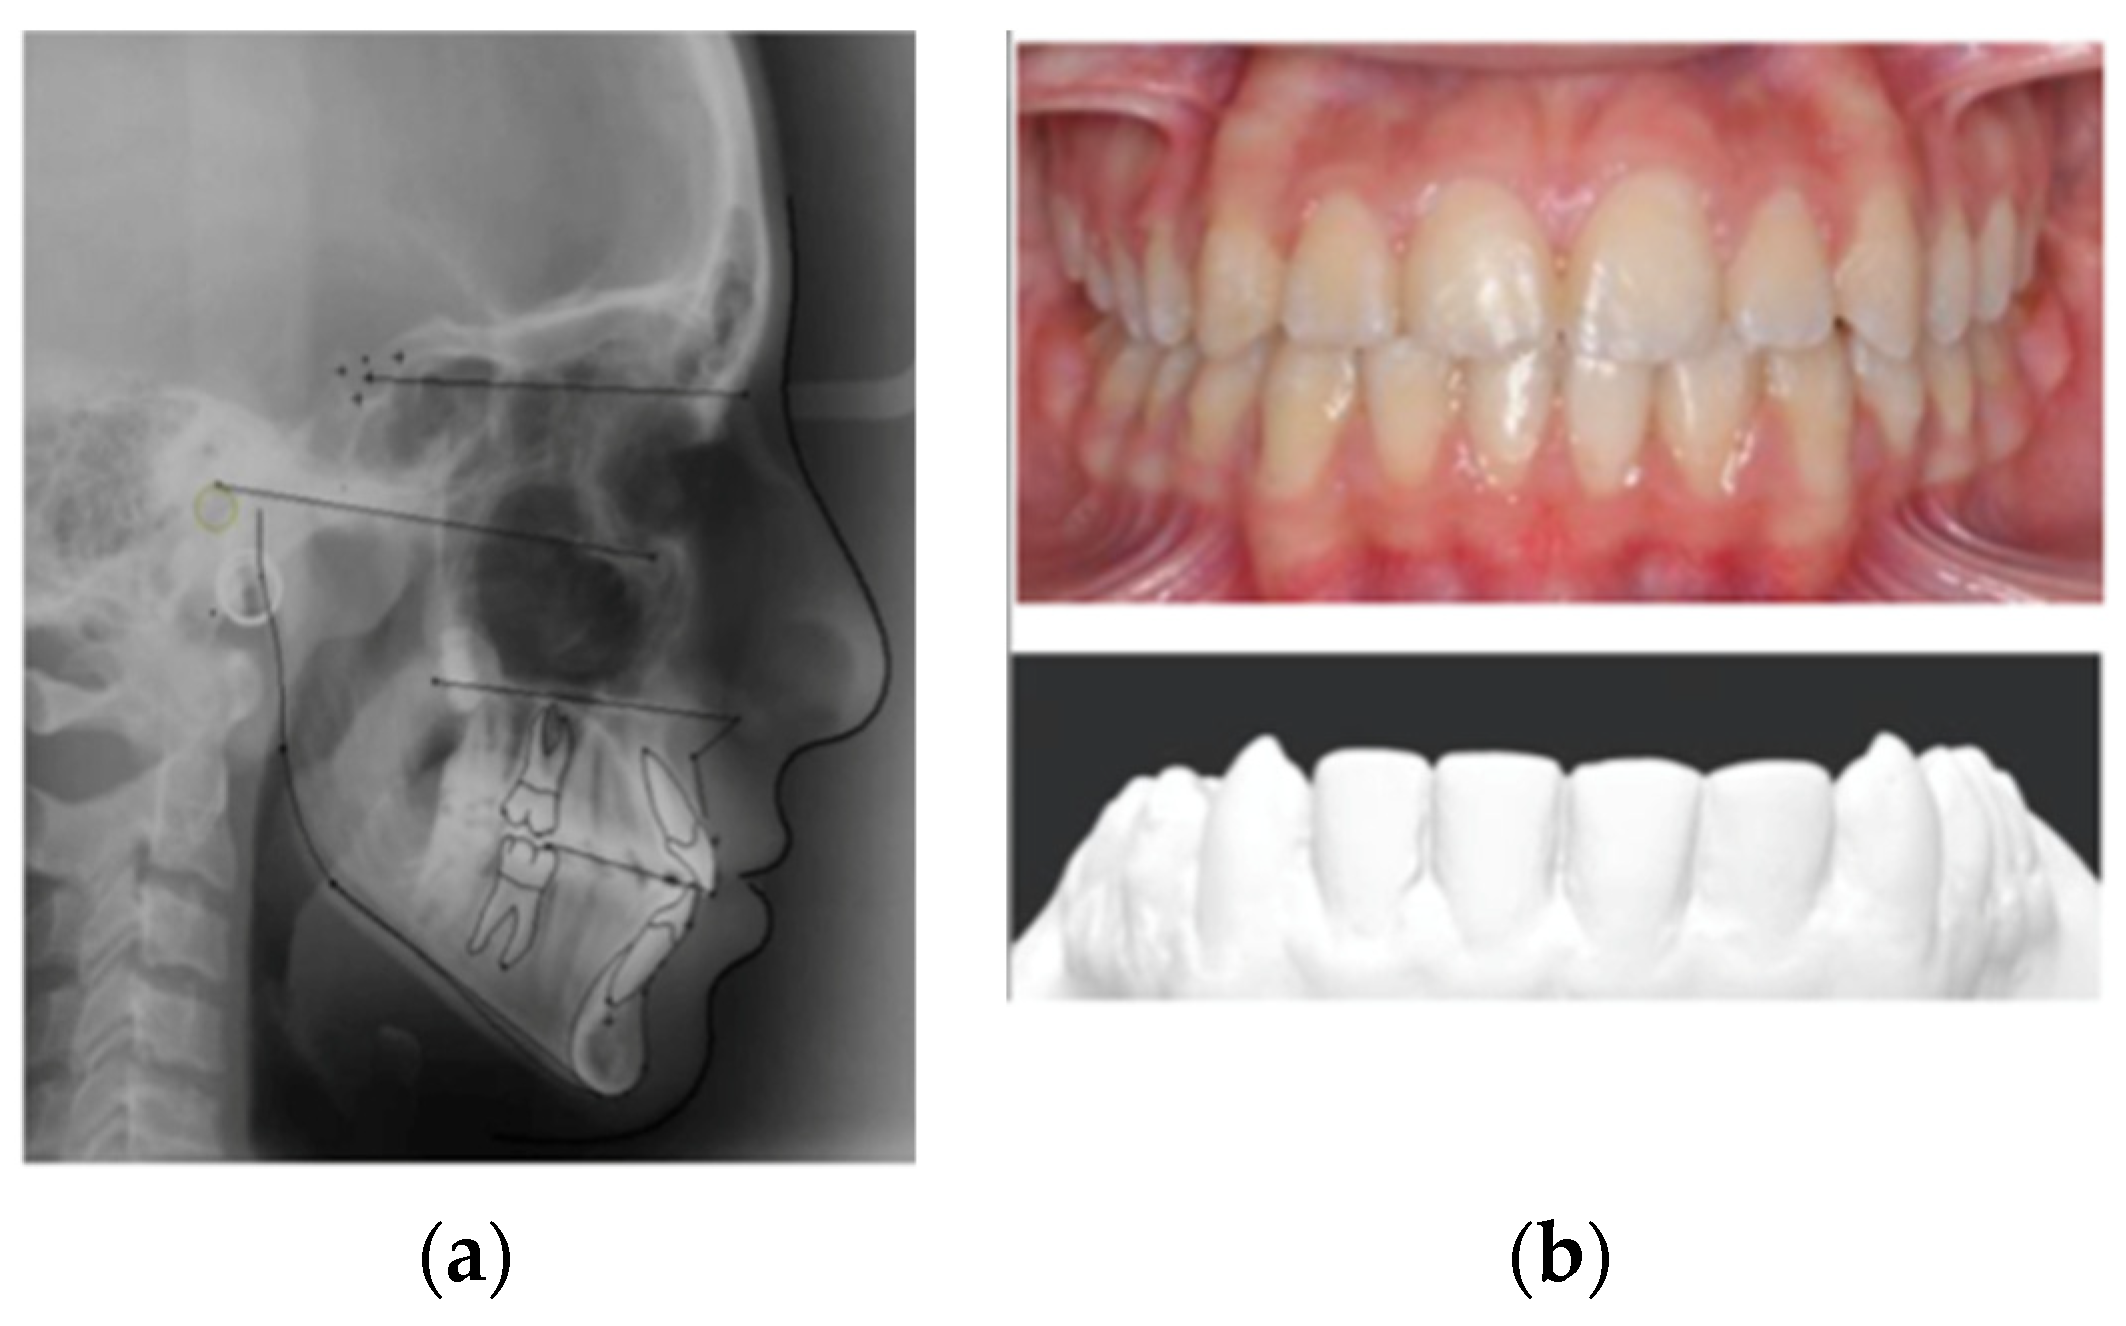

The research protocol of this observational study was approved by the Ethics Committee of the University of Campania Luigi Vanvitelli (Prot. n°18/2018) and a signed informed consent for the use of personal data was available. Data recruitment started in March 2020 and the sample included patients who had consecutively completed their orthodontic treatment between October 2012 and February 2018 at the Orthodontic Program of the University of Campania Luigi Vanvitelli, Naples (Italy). The inclusion criteria were an age between 17 and 35 years; a two-phase non-extraction orthodontic treatment (except for the third molars) with fixed appliances completed at least two years before data collection; the presence of all six dental elements of the frontal upper and lower sextant; and initial and final orthodontic records (lateral cephalometrics, intra/oral photographs, and dental casts of good quality) (Figure 1). The exclusion criteria were systemic pathologies or intake of drugs affecting the periodontal status; periodontitis and/or gingival recessions before the beginning of the orthodontic treatment; and the presence of labial or lingual piercings.

Figure 1.

Post-orthodontic treatment records: cephalometrics (a), photographs, and dental casts (b).